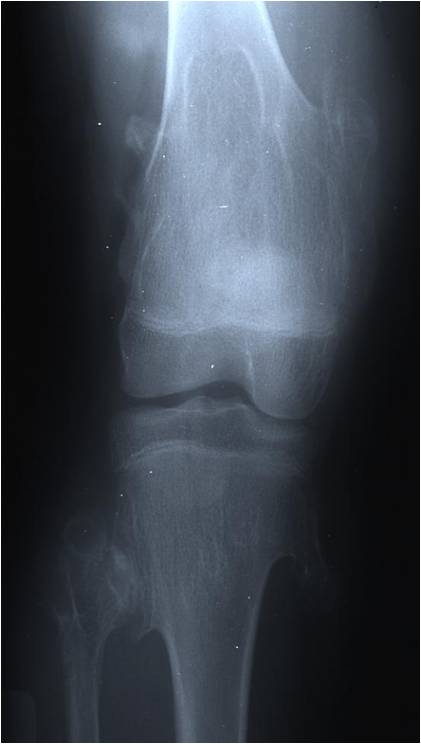

Radiographic Presentation

Plain X-rays:

- Projects from bone with narrow (pedunculated) to broad (sessile) stalk

- Corticomedullary continuity: Medullary bone continuous with that of osteochondroma and cortex blends with that of osteochondroma

- Calcification in cartilaginous cap (“Ring and Arc” and stippled calcifications)

- Lobular growth pattern

- Long bones: arise from metaphysis, grows away from epiphysis toward diaphysis,

- Appendicular skeleton: Femur (30%) Tibia (20%) Humerus (2-%) Hand and Foot (10%)

- Knee area 35% of cases